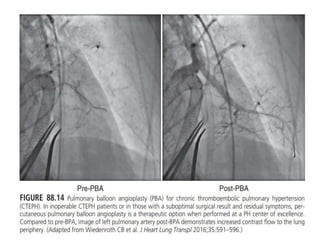

• In patients that are poor surgical candidates, have inoperable disease,

or decline surgery, percutaneous balloon pulmonary angioplasty

(BPA) at an expert referral center is a modern-day treatment option.

• Although angiographic evidence showing improvement in post-

stenotic blood flow following BPA is often evident immediately,

achieving significant clinical benefits from BPA requires multiple

• In patientsthat are poor surgical candidates, have inoperable disease, or decline surgery, percutaneous balloon pulmonary angioplasty (BPA) at an expert referral center is a modern-day treatment option. • Although angiographic evidence showing improvement in post- stenotic blood flow following BPA is often evident immediately, achieving significant clinical benefits from BPA requires multiple procedural attempts, generally requiring separate hospitalizations